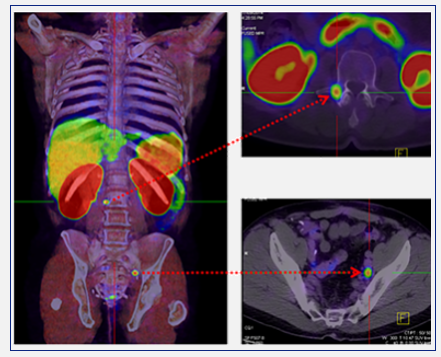

The PET-CT images ​

Positron emission tomography–computed tomography (PET-CT) is a global best practice diagnostic imaging tool that captures three-dimensional images of the body's biological functions. By utilising a small amount of a radiotracer (a radioactive substance that is used in medical imaging*), PET-CT scans can detect areas of abnormal metabolism or function in the body, including fast-growing cancers and infections.

PET-CT scans help doctors pinpoint the location of tumours or cancerous lesions, assess the extent of disease, determine whether lesions are benign or malignant, and identify any potential spread.

PET-CT provides oncologists with accurate information on the extent and severity of disease which enables them to better plan a patients cancer management and treatment, avoiding over or undertreatment, and potentially improving patient outcomes.